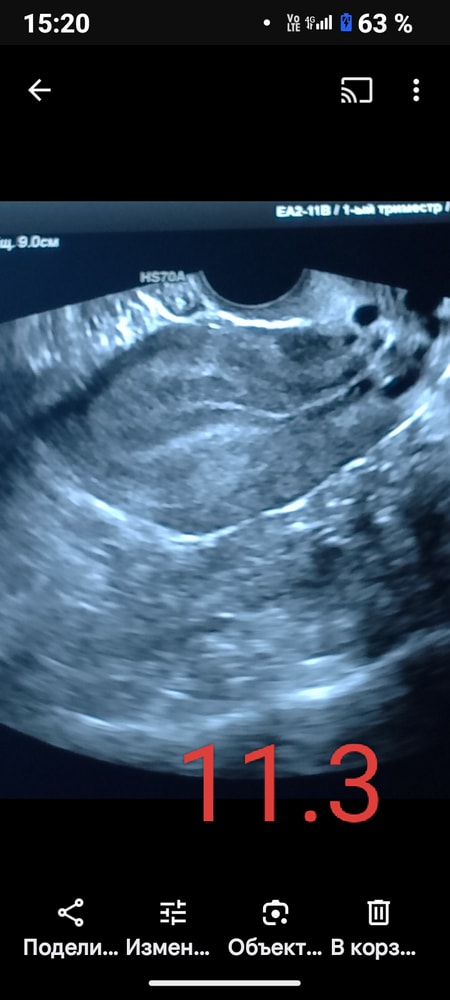

Главное доверяйте ре. После свежего неудачного переноса ре дала отдохнуть 2 месяца и в ец сделать перенос. И вот начинается месяц Х и ме приходят на 5 дней раньше . Делаю узи на 6 дц а эндометрий 2 мм, дф 14мм, 8дц эндометрий 2,2мм, дф 14мм .Я в ужасе, подключаем згт и все ттт выросло, но доминантный фолликул остановился , так что я без жт( хотя все всегда было ок). Я была в дикой истерике и в голос говорила *все в следующем цикле*. И кстати на переносе я была с неполным мочевым и на воду потратили еще минут 30 и перенесли в 121,5